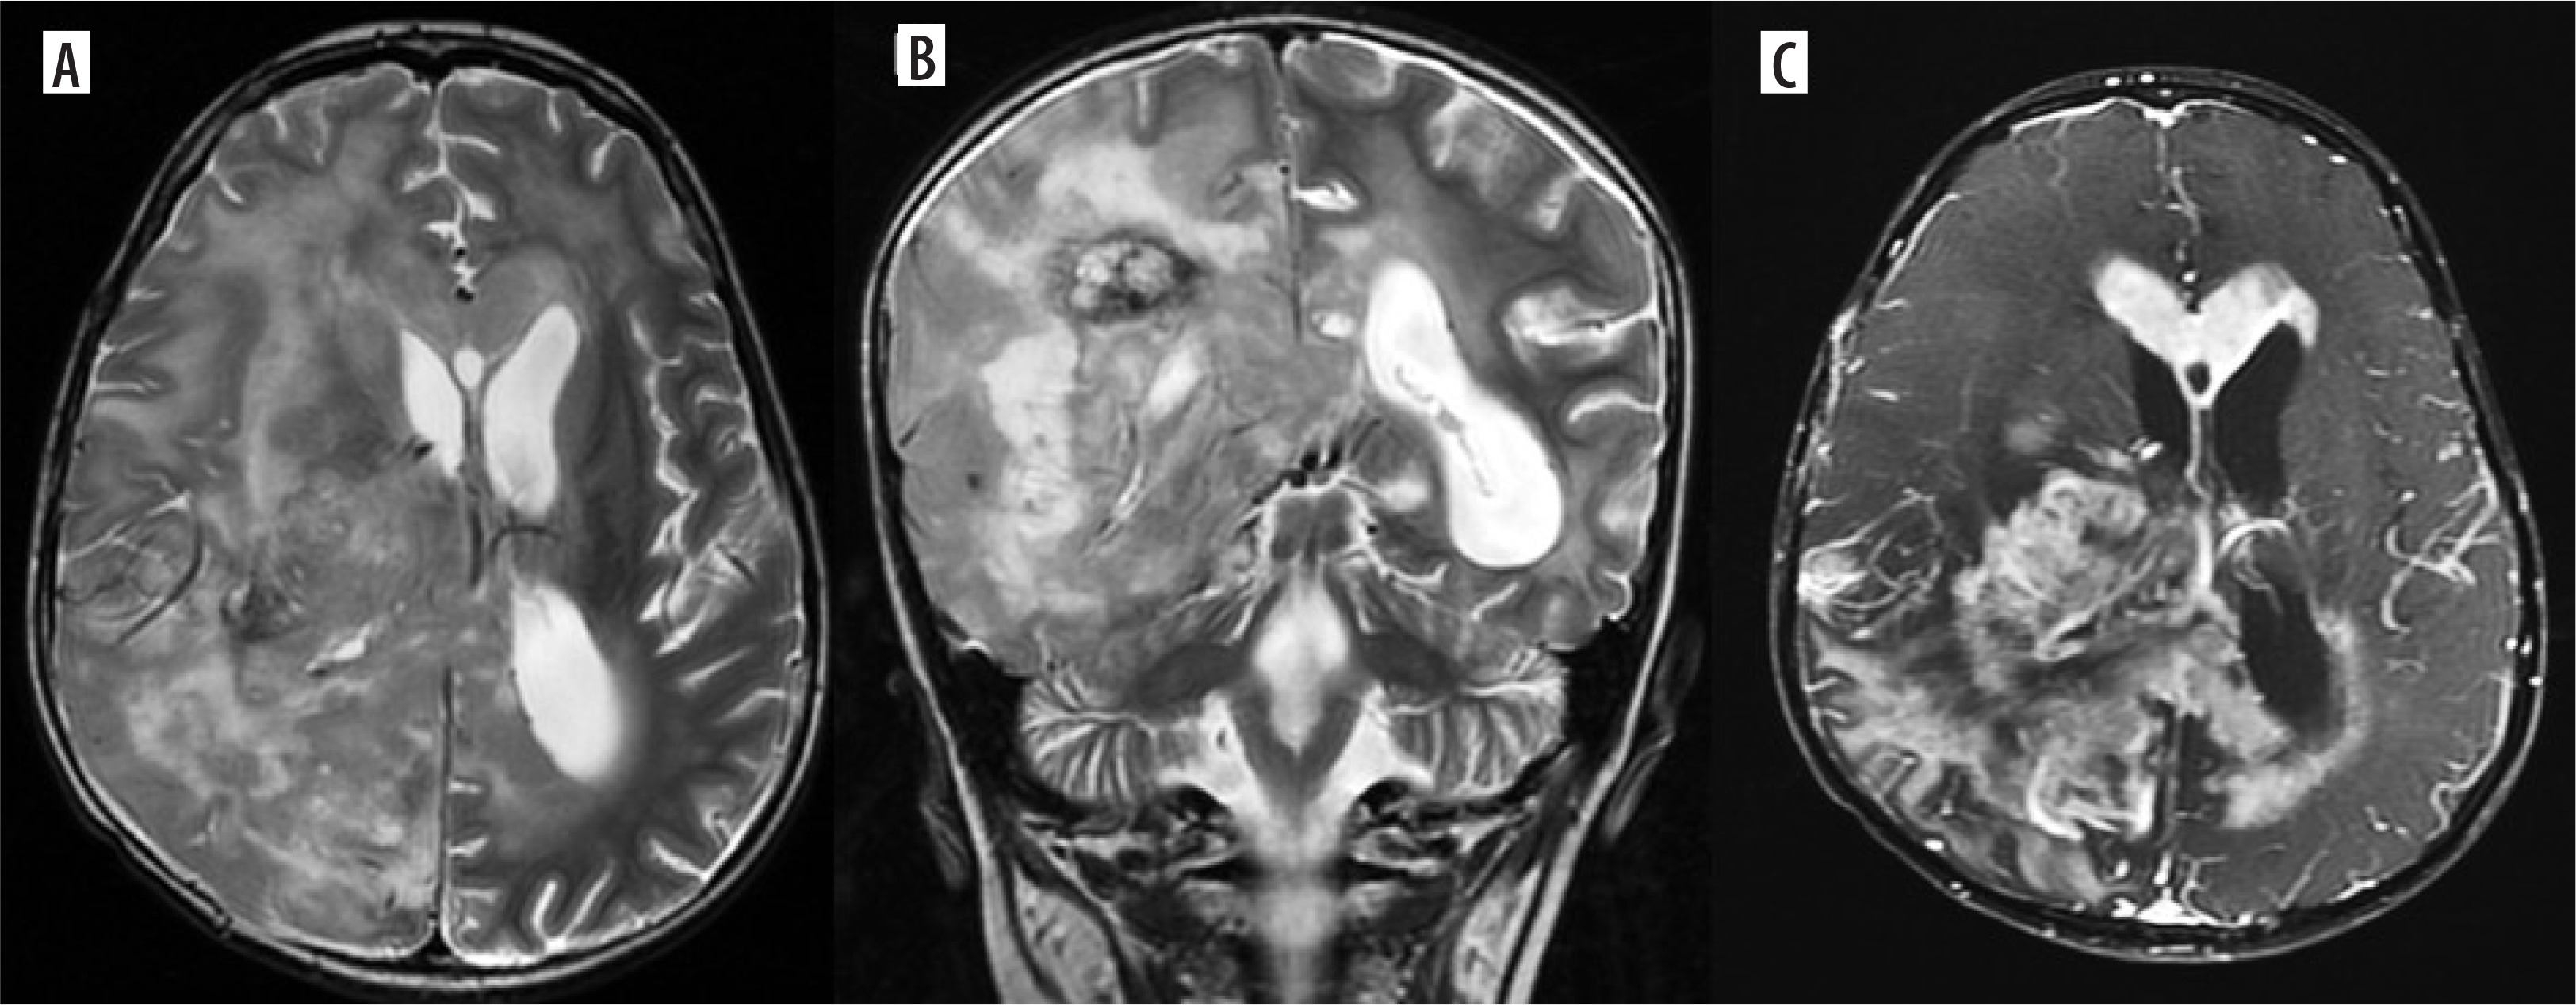

Figure 1

H3K27M mutant diffuse midline glioma. Axial T2, FLAIR and coronal T2WI images (A-D) show diffuse infiltrating midline tumour involving the right thalamus, medial aspect of left thalamus and extending into the midbrain. A few T2 dark areas (red arrow) are noted in the right thalamic region of the lesion, suggestive of high-grade tumour morphology. In the post-contrast study (E), the mass shows no enhancement, characteristic of midline diffuse glioma. This lesion was a histopathologically proven H3K27M mutant